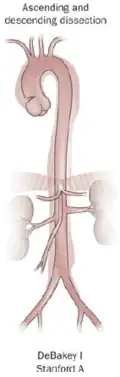

Classification of aortic dissection

Percentage 60% 10–15% 25–30%

Type DeBakey I DeBakey II DeBakey III

Stanford A (proximal) Stanford B (distal)

Several different classification systems have been used to describe aortic dissections. One such classification is based on chronicity and labels aortic dissections as hyperacute (<24 hours duration), acute (2–7 days), subacute (8–30 days), and chronic (>30 days).[20] The systems commonly in use are based on either the anatomy of the dissection or the duration of onset of symptoms before the presentation. The Stanford system is used more commonly now, as it is more attuned to the management of the patient.[38]

The DeBakey system, named after cardiothoracic surgeon Michael E. DeBakey, is an anatomical description of the aortic dissection. It categorizes the dissection based on where the original intimal tear is located and the extent of the dissection (localized to either the ascending aorta or descending aorta or involving both the ascending and descending aorta).[39]

• Type I – originates in ascending aorta, and propagates at least to the aortic arch and often beyond it distally. It is most often seen in patients less than 65 years of age and is the most lethal form of the disease.

• Type II – originates in the ascending aorta and is confined to it.

• Type III – originates in the descending aorta and rarely extends proximally, but will extend distally. It most often occurs in elderly patients with atherosclerosis and hypertension.

The Stanford classification is divided into two groups, A and B, depending on whether the ascending aorta is involved.[40]

• A – TAAD involves the ascending aorta and/or aortic arch, and possibly the descending aorta. The tear can originate in the ascending aorta, the aortic arch, or more rarely, in the descending aorta. It includes DeBakey types I and II.

• B – TBAD involves the descending aorta or the arch (distal to the left subclavian artery), without the involvement of the ascending aorta. It includes DeBakey type III.

The Stanford classification is useful as it follows clinical practice, as type A ascending aortic dissections generally require primary surgical treatment, whereas type B dissections generally are treated medically as initial treatment with surgery reserved for any complications.[41]